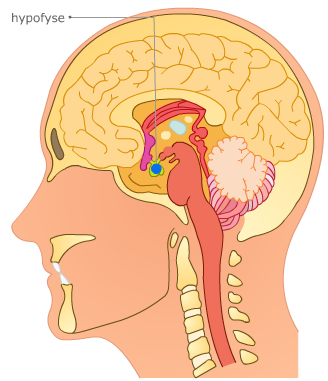

De menstruatiecyclus wordt geregeld door hormonen. Twee hormonen uit de hypofyse spelen een belangrijke rol:

De menstruatiecyclus wordt geregeld door hormonen. Twee hormonen uit de hypofyse spelen een belangrijke rol:

het follikel stimulerend hormoon (FSH) en het lute niserend hormoon (LH).

De hypofysehormonen stimuleren de rijping van een eicel in de eierstokken.